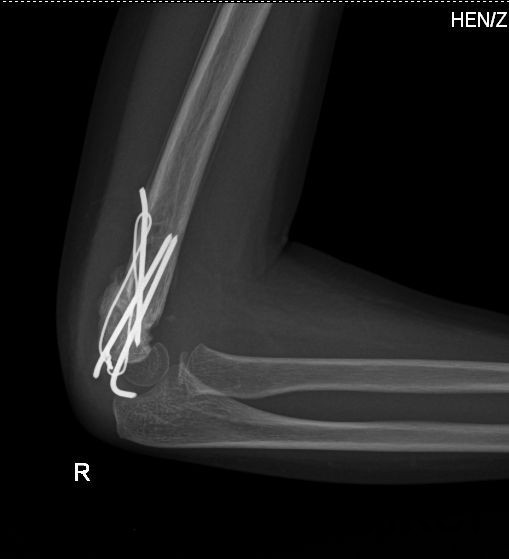

诊断:右侧肱骨髁上骨折 治疗:全麻下行“右侧肱骨髁上骨折切复内固定术

1、出院后继续功能锻炼,避免剧烈活动及外伤; 2、加强营养,促进骨折愈合; 3、定期复查,出院后2周来院复查; 4、住院及康复期间需陪护护理; 5、骨折愈合后需二次手术取内固定